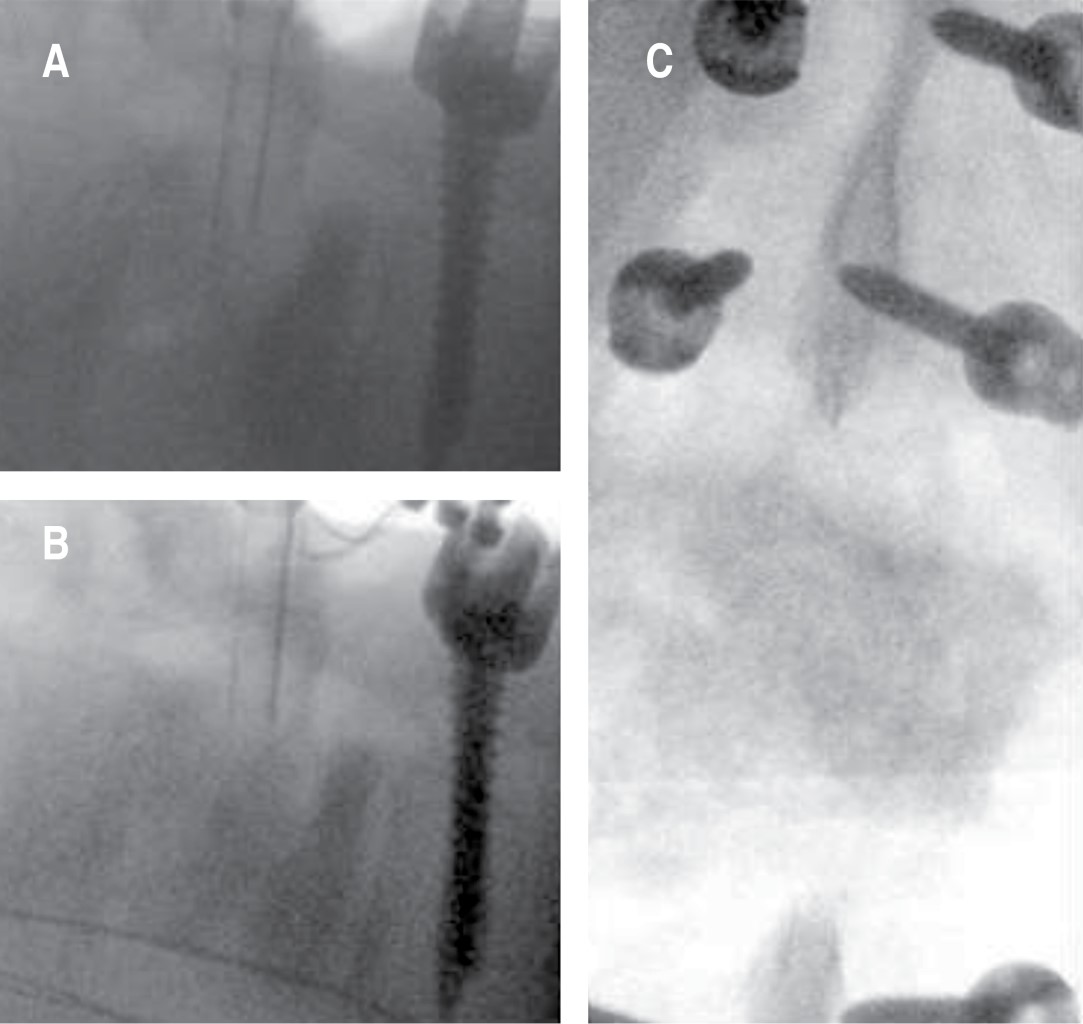

Se realizó artrodesis toracopélvica de T10 a iliacos, por abordaje posterior con doble barra de titanio y conectores, con una guía 3D y agujas de Kirschner, se realizó colocación de tornillos sacroilíacos; se resecó callo óseo y, con ayuda de un embudo a través del pedículo derecho de L3, se colocó injerto óseo autólogo en el espacio del cuerpo de L3 con fluoroscopio. Sangrado de 1,200 ml, se transfundió un paquete globular. El paciente egresó a los tres días (Figuras 5, 6 y 7).